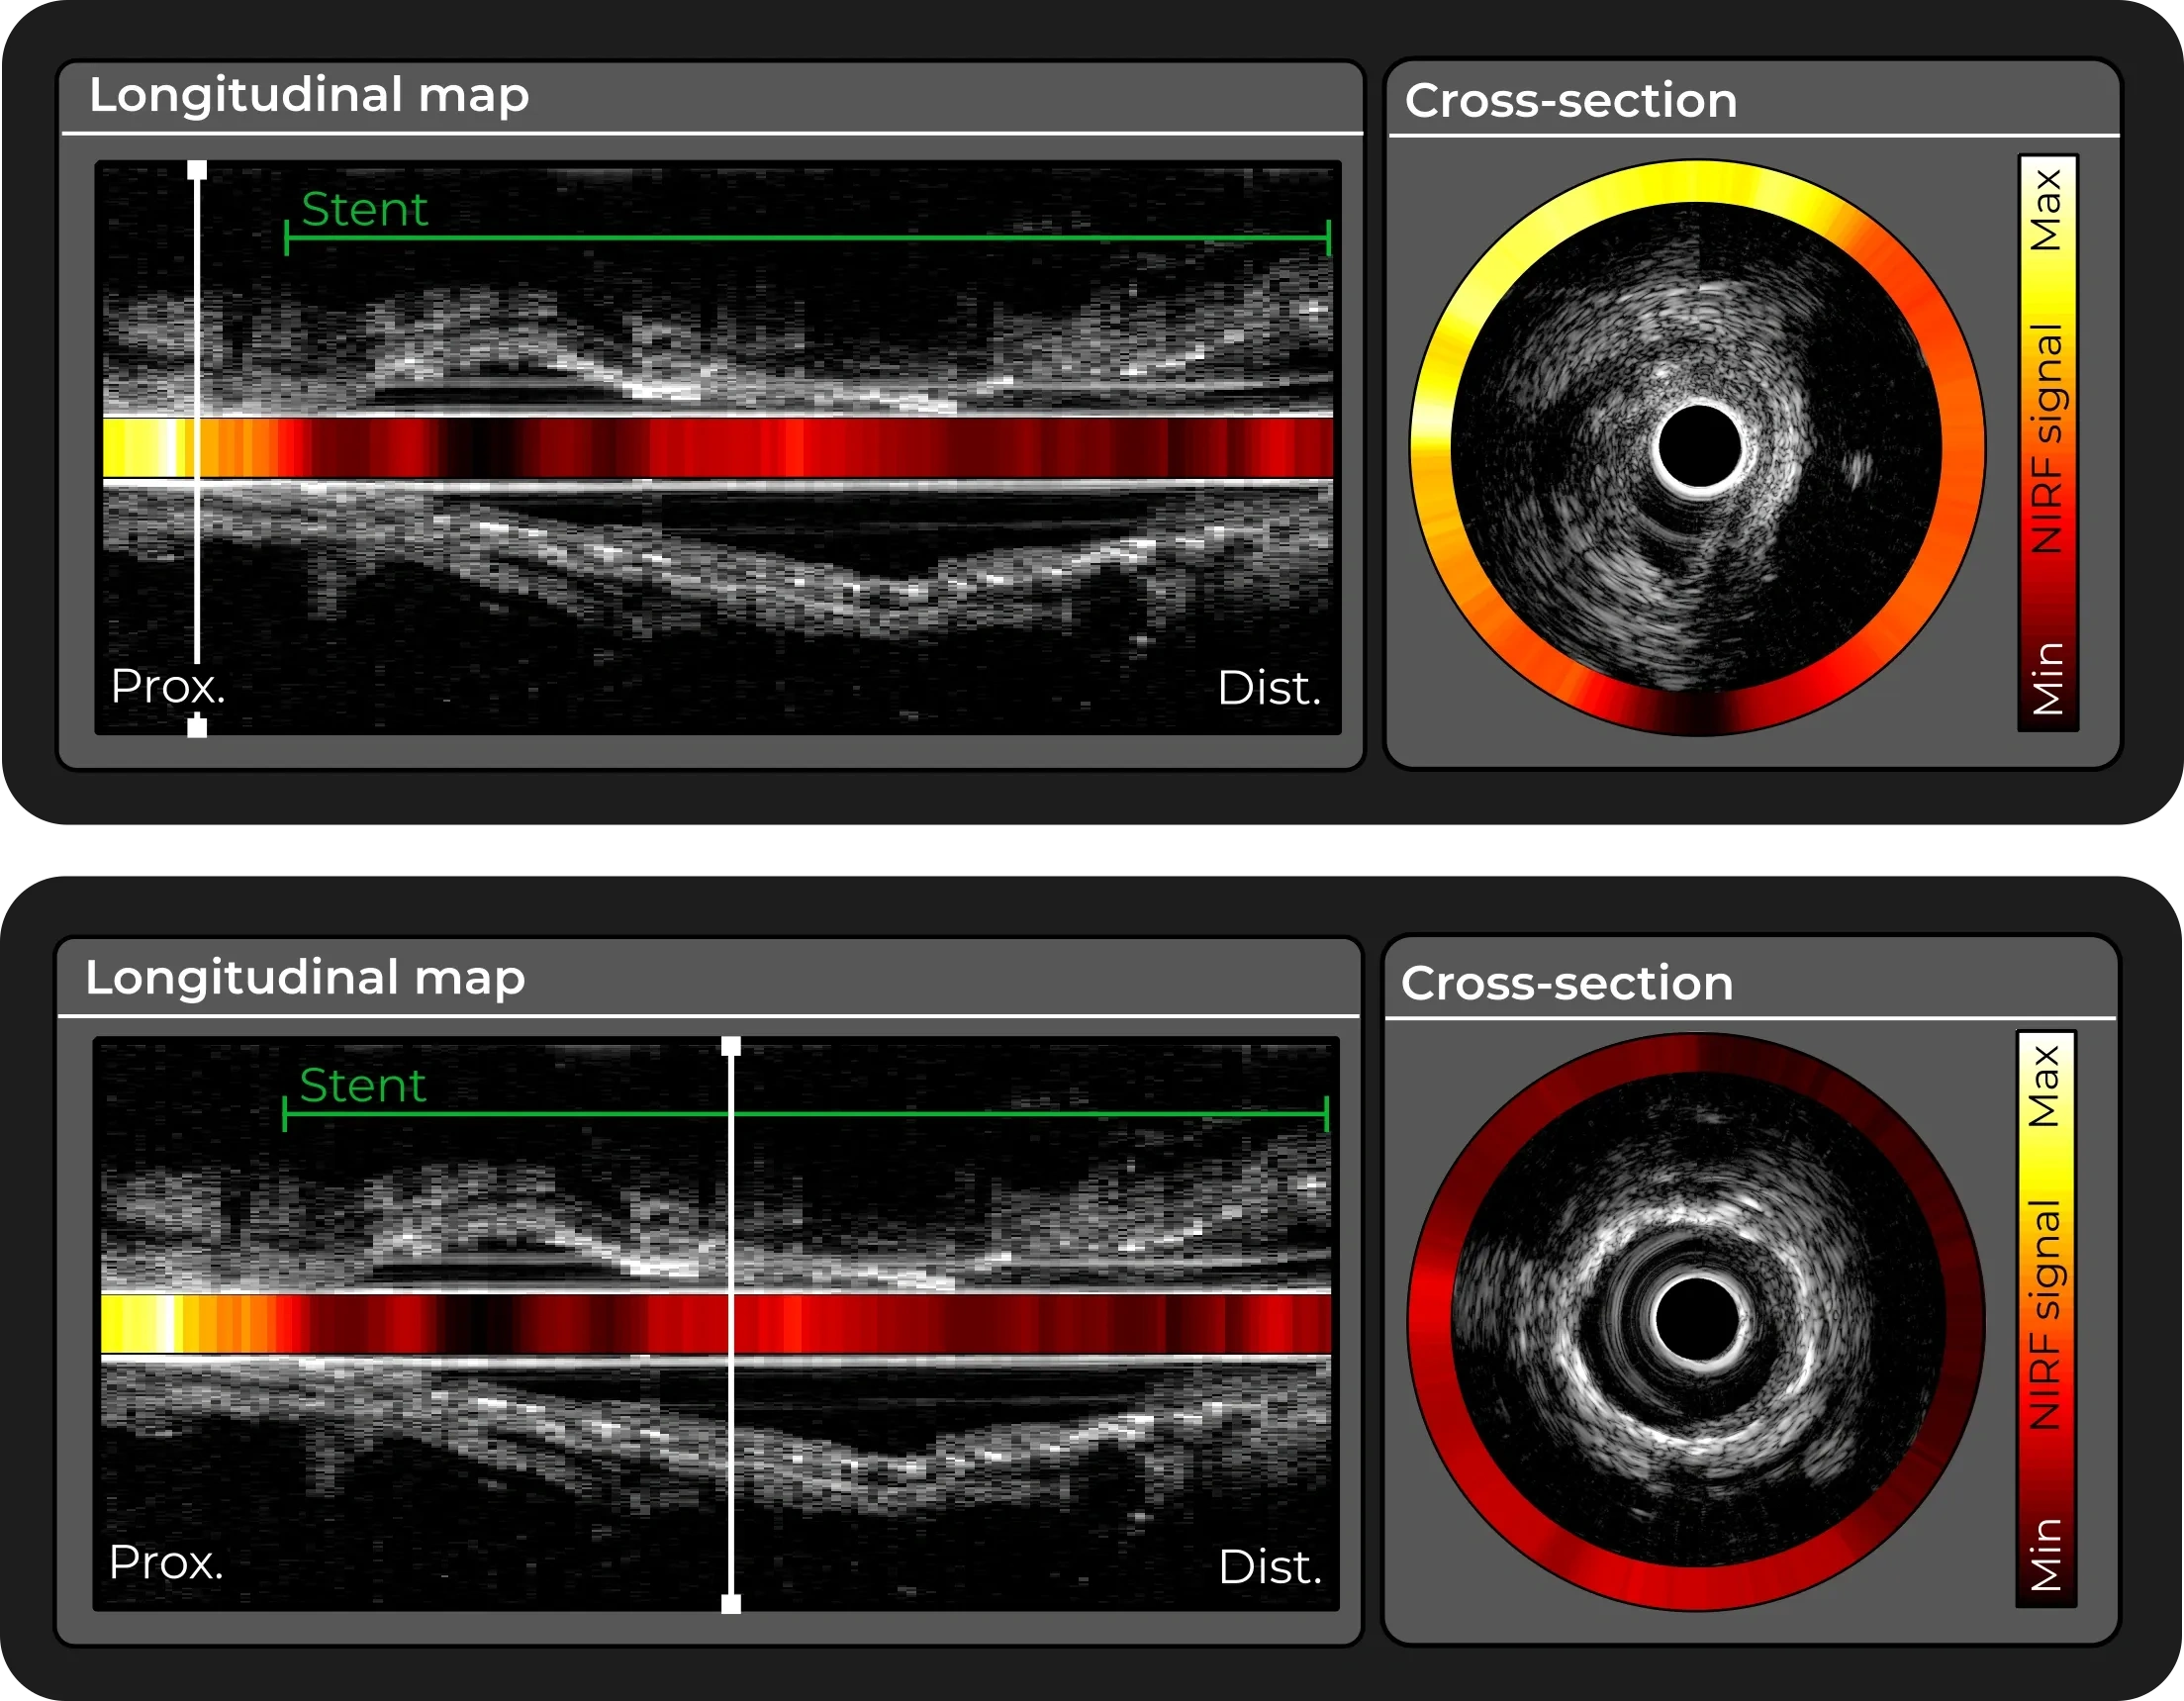

Combining IVUS - current clinical standard - with Near-infrared Fluorescence (NIRF) to look beyond vascular anatomy and improve PCI guidance.